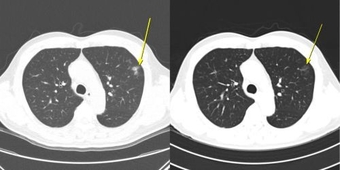

연구팀은 치료 중 나타난 이상반응 양상에 따라 환자를 ▲이상반응이 전혀 없는 ‘무이상반응군’ ▲임상 증상이나 혈액검사 이상을 동반한 ‘증상성 이상반응군(증상군)’ ▲증상은 없지만 CT에서 폐 주변부 미세 염증성 음영, 일시적 대장벽 비후, 장간막 염증, 반응성 림프절 종대 등 면역반응으로 해석되는 변화만 나타난 ‘무증상 영상 이상반응군(무증상 영상군)’으로 분류했다. 전체 198명 중 무증상 영상군은 12명, 증상군은 56명, 무이상반응군은 130명이었다.

▲ 무증상 일시적 면역관련 폐렴 사례